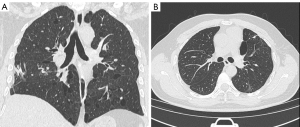

Case A was a 58-year-old man. On October 27, 2020, the patient came to the First Affiliated Hospital of Henan University of Science and Technology for the first time for repeated spontaneous pneumothorax, which he had had four times in total. He had no history of smoking or occupational dust exposure. Multislice CT of the chest showed predominantly pulmonary cysts in the lower lungs and subpleural distribution (Figure 1A,1B). This patient has a total of 241 pulmonary cysts in both lungs. Pulmonary cysts in the lower lungs accounted for 63% (153/241), and subpleural cysts accounted for 68% (164/241). The largest cyst, measuring 52 mm ×48 mm ×112 mm in diameter, was located in the left lower lung. The large cysts near the spine of the bilateral lower lobes were fusiform (Figure 1C). Pulmonary vessels could be observed inside some cysts (Figure 1D). In the hand examination, the patient showed bilateral finger flexion contracture and could not extend the fingers fully. Digital radiography showed finger deformity and narrowing of the finger joint space (Figure 2). No substantial lesions were found in the heart and kidney ultrasound.

Case B was the 29-year-old son of case A. He first came to our hospital on May 19, 2014 with spontaneous pneumothorax, which he had had three times in total. The patient had no history of smoking or occupational dust exposure. Chest CT showed pulmonary cysts, which were mainly distributed in the lower lung and bilateral subpleural lungs (Figure 3A). This patient has a total of pulmonary cysts in both lungs. Pulmonary cysts in the lower lungs accounted for 52% (43/82) and subpleural accounted for 71% (58/82). The largest cyst, measuring 35 mm ×21 mm ×44 mm in diameter, was in the left upper lobe (Figure 3B). In the hand examination, the patient showed double finger deformities similar to those of his father. The patient underwent bullae resection, and pathological examination of the resected specimens confirmed lung bullae (Figure 4).